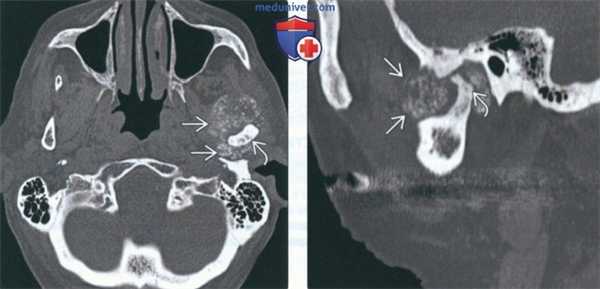

(Слева) На аксиальной КТ в костном окне визуализируется типичная хондросаркома ВНЧС с множественными кальцинатами. Мыщелок нижней челюсти слева неравномерно склерозирован, в ВНЧС и вокруг него визуализируются множественные мелкие очаговые кальцинаты.

(Справа) На сагиттальной реформатированной КТ у этого же пациента определяется деформация мыщелка. Некоторые кальцинаты, вероятно, находятся в мягкотканном компоненте за пределами сустава.

(Слева) На аксиальной КТ с КУ в мягкотканном окне визуализируется гиподенсная опухоль (хондросаркома без включений кальция), окружающая ветвь нижней челюсти и распространяющаяся вокруг венечного отростка и мыщелка.

(Справа) На аксиальной КТ в костном окне определяется вздутие мыщелка и шейки нижней челюаи с наличием хондроидных кальцинатов. Отсутствие типичных для хондросаркомы кальцинатов в мягкотканном компоненте затрудняет диагностику.

(Слева) КТ в костном окне, аксиальная проекция. Типичная хондросаркома левого височно-нижнечелюстного суаава. Мыщелок нижней челюсти склерозирован и имеет неправильную форму, внутри и вокруг сустава рассеянны множественные кальцификаты. И хотя в данном случае достаточно сложно дифференцировать заболевание от синовиального хондроматоза, в обоих случаях лечение должно быть хирургическим, а точный диагноз будет установлен после гистологического исследования.

(Справа) Реконструкция в сагиттальной плоскости, этот же пациент. Мыщелок деформирован, а часть кальцификатов находится в мягких тканях вне сустава.

(Слева) КТ с КУ, мягкотканное окно. Другой пример хондросаркомы жевательного пространства, на этот раз без кальцификатов. Образование низкой плотности окружает ветвь нижней челюаи и распространяется вокруг венечного отростка и мыщелка.

(Справа) КТ в костном окне, аксиальная проекция. Мыщелок и шейка нижней челюсти деформированы и содержат кальцификаты. Отсутствие характерных кальцификатов в мягкотканной части опухоли делает постановку диагноза затруднительной.